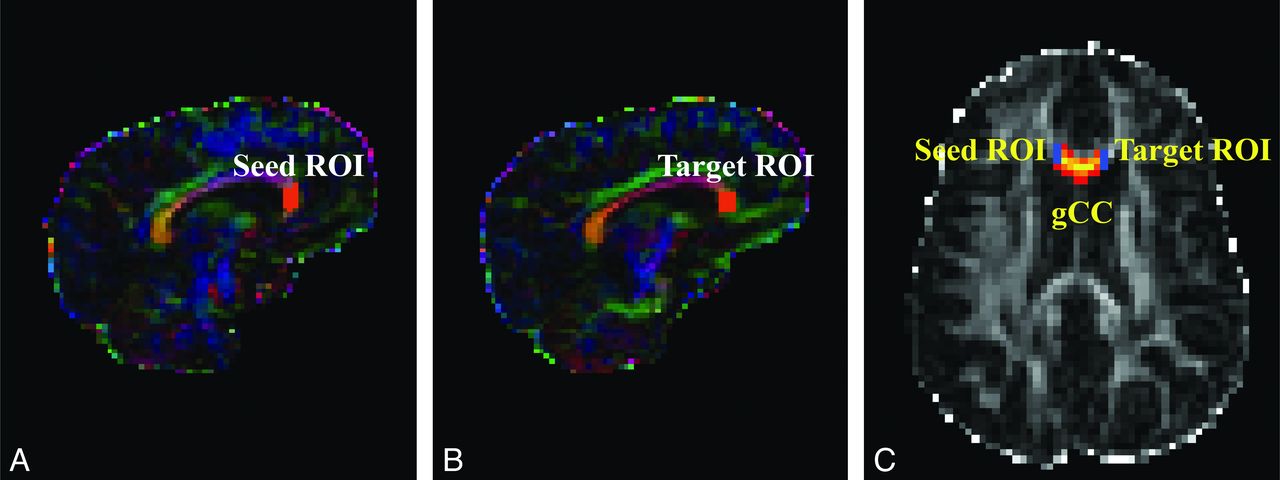

At each voxel, the Bayesian Estimation of Diffusion Parameters Obtained by using Sampling Techniques (BEDPOSTX) function in FSL was used to build up the distributions on diffusion parameters on the basis of the Markov Chain Monte Carlo sampling.11 The outputs of the BEDPOSTX were used to compute the PDT by using Probtrackx12 in FSL. The seed and target masks used in the PDT for genu of the CC were created on sagittal sections as illustrated in Fig 1. The 2 masks for the left or right mCST were created on axial sections placed between 1 section below the body of the corpus callosum and the entry of the posterior limb of the internal capsule to the cerebral peduncle (Fig 2). All masks were delineated by 1 operator (W.Y.) and confirmed by 3 pediatric radiologists (R.C.M., J.S.S., and B.V.J.) and 2 pediatric neurosurgeons (F.T.M., D.D.L.).

DTI maps demonstrating seed and target masks and resultant probabilistic fiber tracking of the genu of the CC in representative participants. A–C, hydrocephalus. A and B, Color-coded FA maps. C, FA map. The masks shown in orange in the sagittal maps can be seen as short blue lines on axial map.

The connectivity index maps (Figs 1 and 2) are the connectivity distribution maps with the value at each voxel being the sum of the sample streamlines passing through the voxel. In the present study, we defined a seed mask and a target mask for each subject on the basis of anatomic landmarks, to restrict the tractography in all the tracts examined to yield the specific tracts of interest. The connectivity measure is a quantification of the strength, or probability, of the connectivity for all those connections initiated from the seed voxels and reaching the target masks. Similar approaches based on PDT have been adopted by other studies to investigate the pathologic progression in amyotrophic lateral sclerosis,14 to contrast the organization of prefrontal projection pathways in humans and macaque monkeys.20

In the present study, the histogram based on the aggregated normalized CI measures showed that children with hydrocephalus had a lower percentage of voxels with higher connectivity and a higher percentage of voxels with low connectivity in all 3 tracts examined. The comparison of the within-tract summary connectivity measure between the 2 groups showed a consistent significant decrease in normalized CI values in children with hydrocephalus. As expected, examination of the connectivity index maps (Figs 1 and 2 as examples) showed that the voxels with high connectivity were located in the central portion of the tracts, while the voxels at the peripheral areas of a tract tended to have lower connectivity. We examined the summary connectivity measure (normalized CI) not only at the median but also at the lower and upper quartile values. The fact that the group contrast was significant at all 3 quartile levels indicates that this summary connectivity index, normalized CI, is sensitive to the pathology resulting from hydrocephalus throughout different portions of WM tracts in children with hydrocephalus.